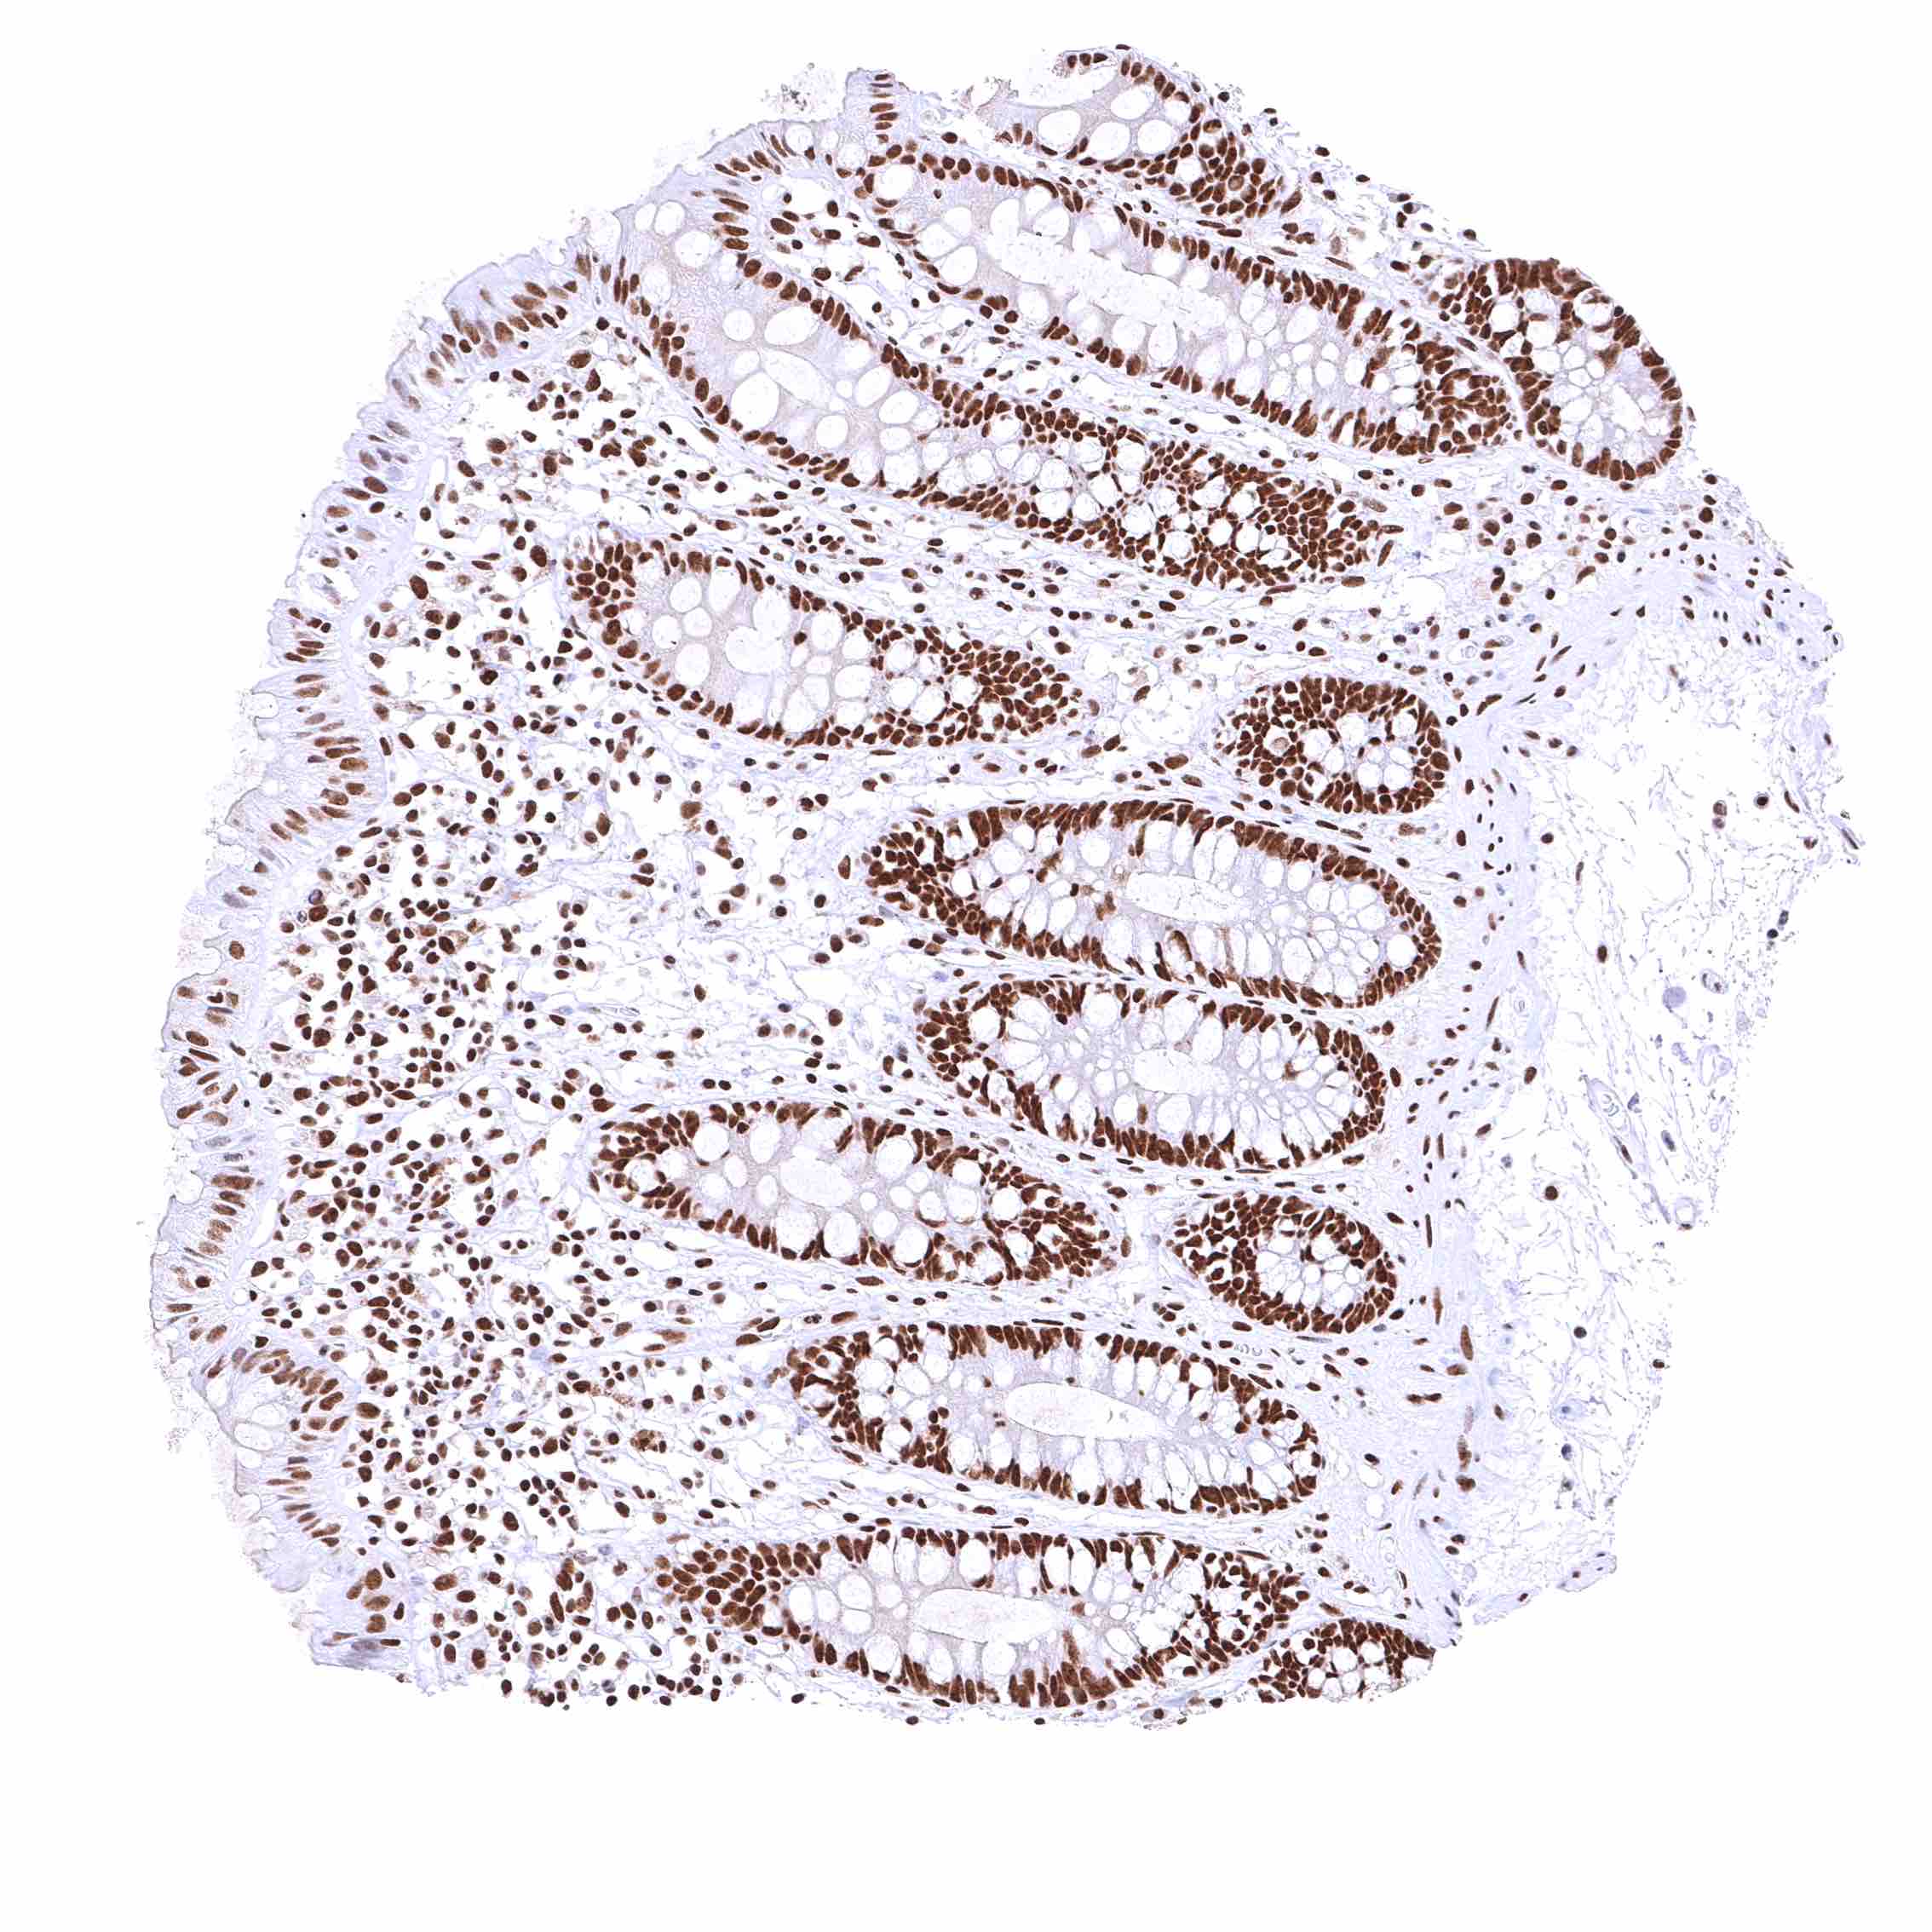

BRD4 antibody [HMV4275] HistoMAX™

Colon descendens, mucosa – Nuclear BRD4 staining of surface epithelial cells is weaker than in crypts.